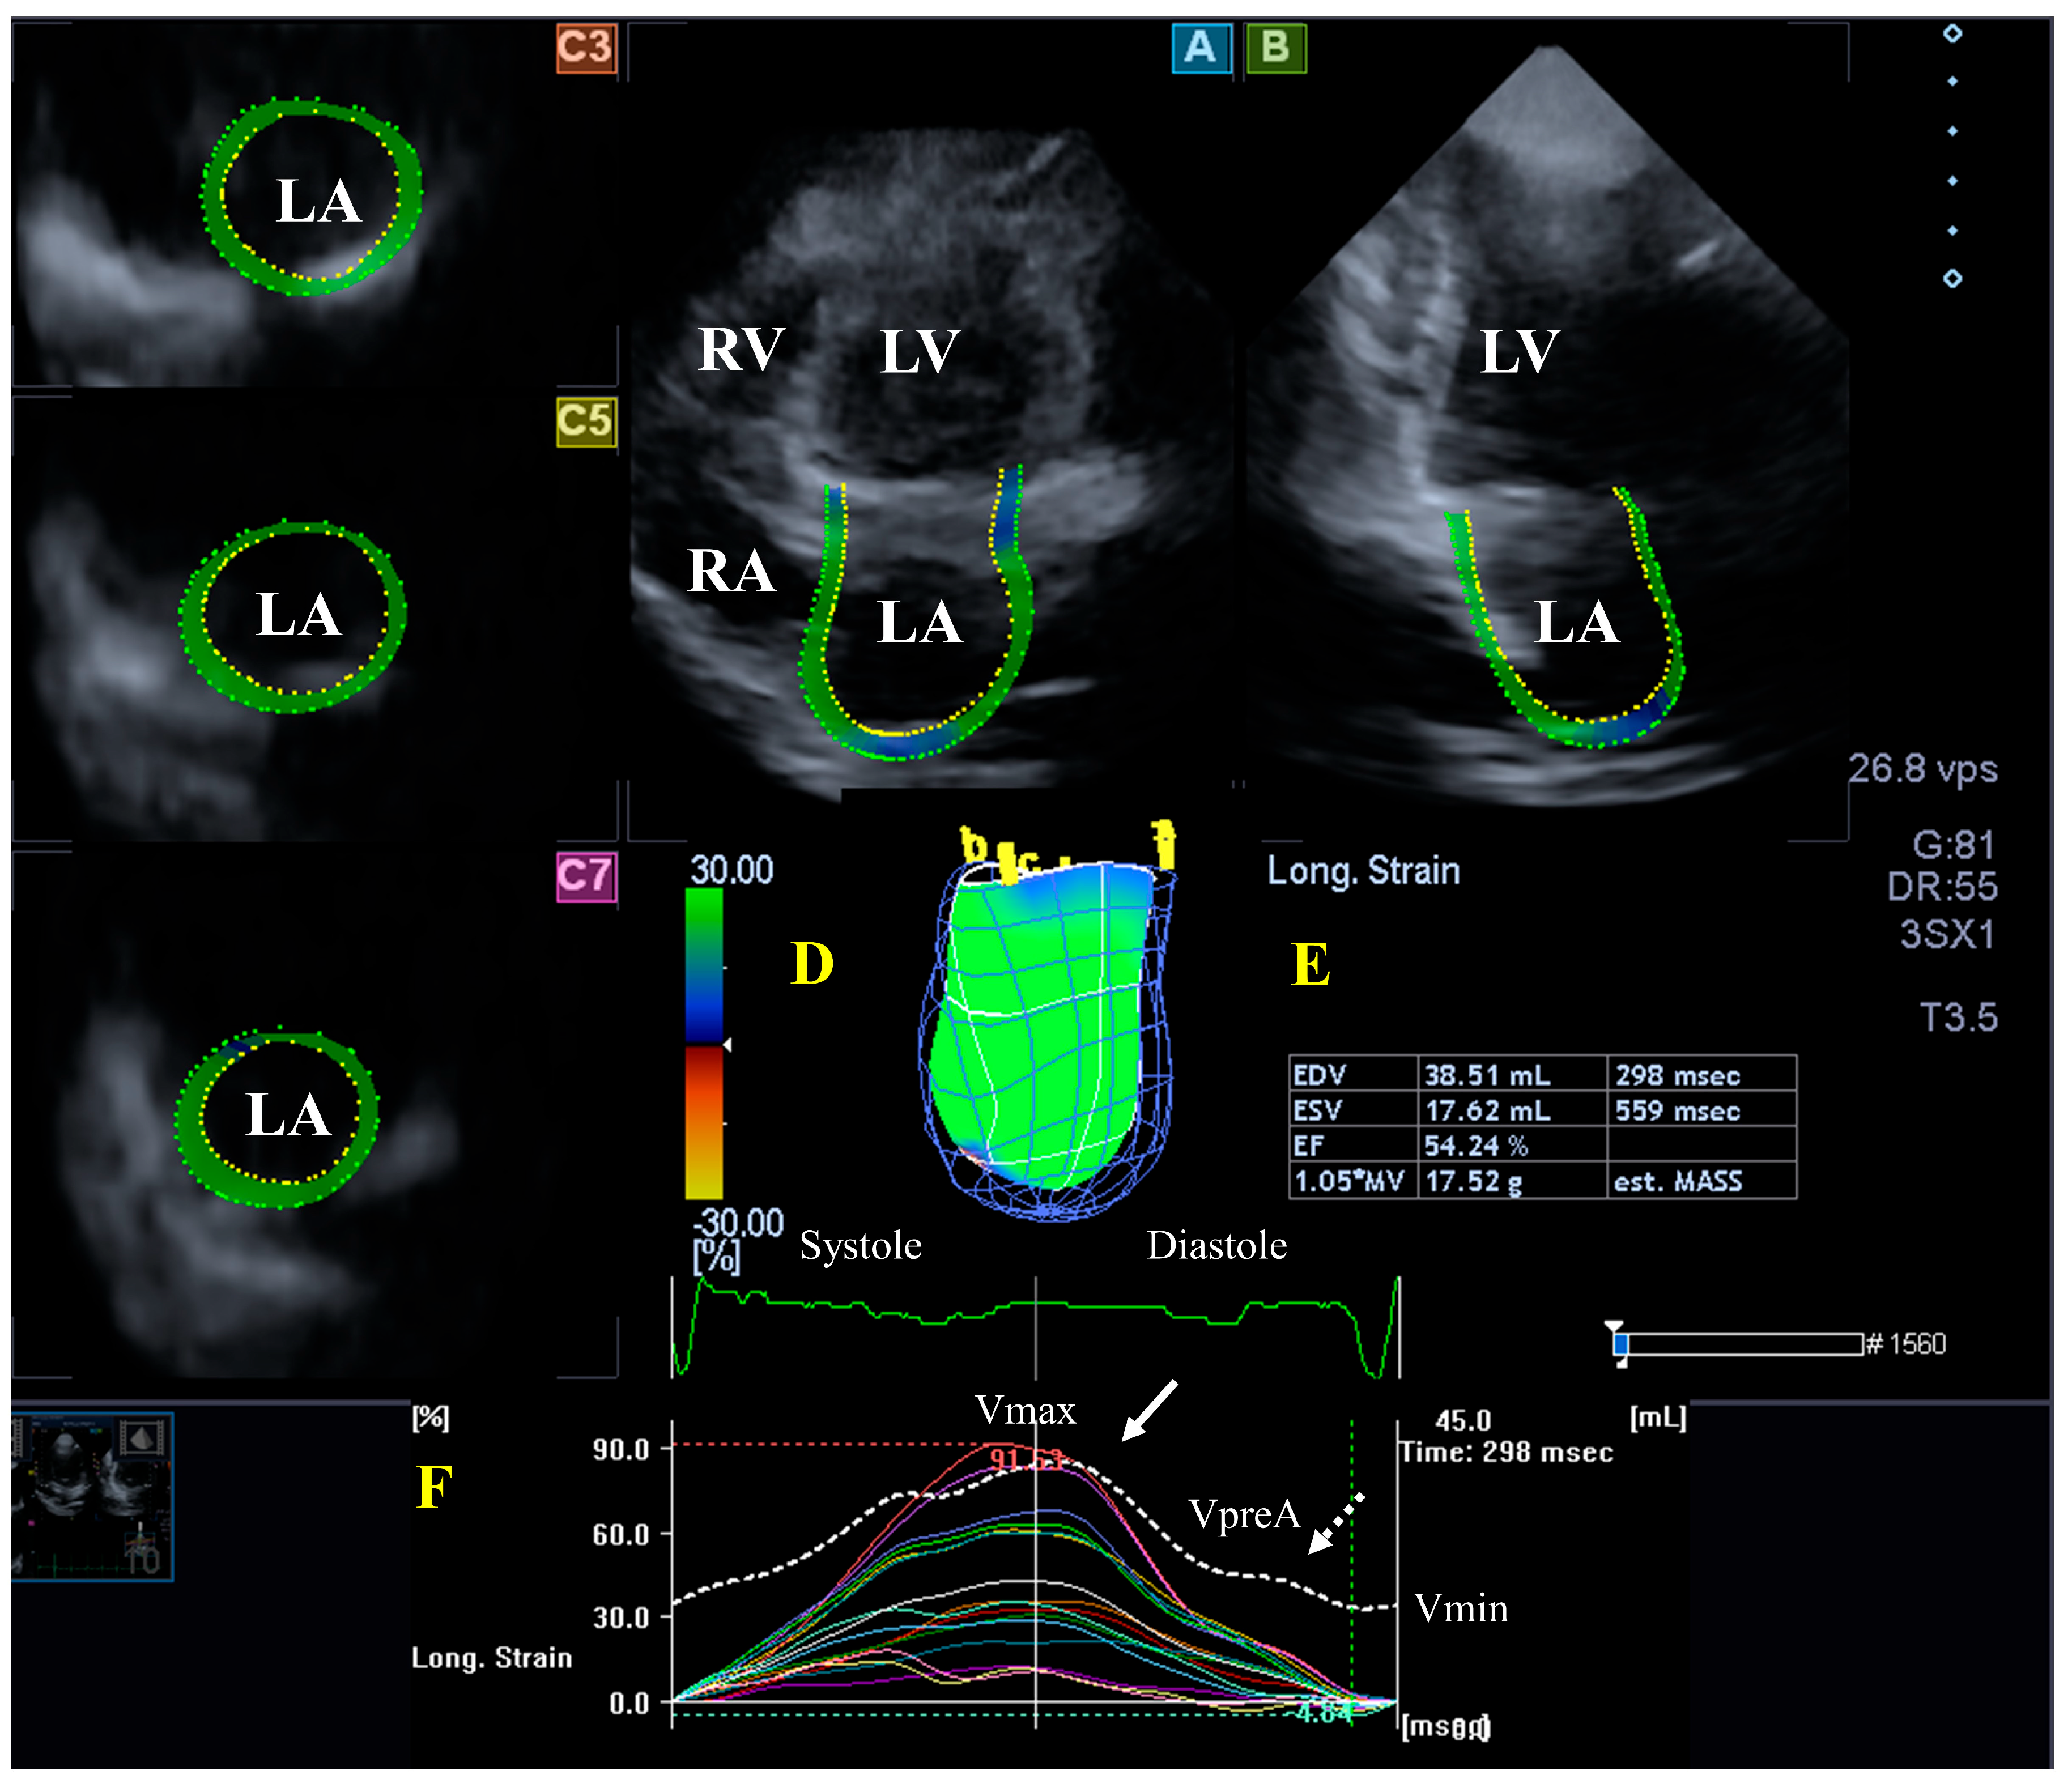

Figure 1.

Evaluation of the left ventricle (LV) by three-dimensional (3D) speckle-tracking echocardiography. Typically, several views are automatically created during the LV assessment using a dedicated vendor-provided software: apical longitudinal four-chamber (A) and two-chamber (B) views and apical (C3), midventricular (C5), and basal (C7) short-axis views. In a 3D LV model (D), LV volumes, ejection fraction, and mass (E) and the apical (white arrow) and basal (white dashed arrow) rotations of the LV (F) are seen with time, as well as the LV global (white curve) and segmental (colored curves) radial (G), longitudinal (H) and circumferential (I) strain curves with time, and an LV volume changes curve with time (dashed white curve) are presented. Abbreviations: RA = right atrium; RV = right ventricle; MASS = LV muscle mass; LA = left atrium; LV = left ventricle; EF = ejection fraction; EDV = end-diastolic volume; and ESV = end-systolic volume.

The LA is on the left posterior side of the heart and is responsible for regulating one-way blood flow between the pulmonary veins and the LV through the MV in normal circumstances. The LA has circumferential (e.g., interatrial band, located at the base) and longitudinal (e.g., septoatrial band, located parietally) muscle bands. The rim of the oval fossa is essential, as the main muscles of the atrium are attached to it. LA function changes with the heart cycle: it acts as reservoir in LV systole, a conduit in early LV diastole, and an active contractile chamber in late LV diastole. The maximum LA volume is detected during end-systole; a pre-atrial contraction volume is seen in early diastole; and the minimal LA volume is measured in late diastole. Emptying fractions and stroke volumes can be calculated from the LA volumes characterizing all phases of LA function. Moreover, LA wall contractility/relaxation during the cardiac cycle could also be characterized by LA strains, similarly to LV [11,32,33]. (Figure 2).

Figure 2.

Evaluation of the left atrium (LA) by three-dimensional (3D) speckle-tracking echocardiography. Typically, several views are automatically created during LA assessment using a dedicated vendor-provided software: apical longitudinal four-chamber (A) and two-chamber (B) views and basal (C3), midventricular (C5), and superior (C7) short-axis views. In a 3D LA model (D), the LA volumes (E), the LA global (represented by the white curve) and segmental (represented by colored curves) longitudinal (F) strain curves with time, and the LA volume changes’ curve with time (dashed white curve) are also presented. Abbreviations: LA = left atrium; LV = left ventricle; EF = ejection fraction; EDV = end-diastolic volume; ESV = end-systolic volume; MASS = LA muscle mass; RA = right atrium; RV = right ventricle; Vmin = minimum LA volume at end-diastole; VpreA = LA volume before atrial contraction at early diastole; and Vmax = maximum LA volume at end-systole.